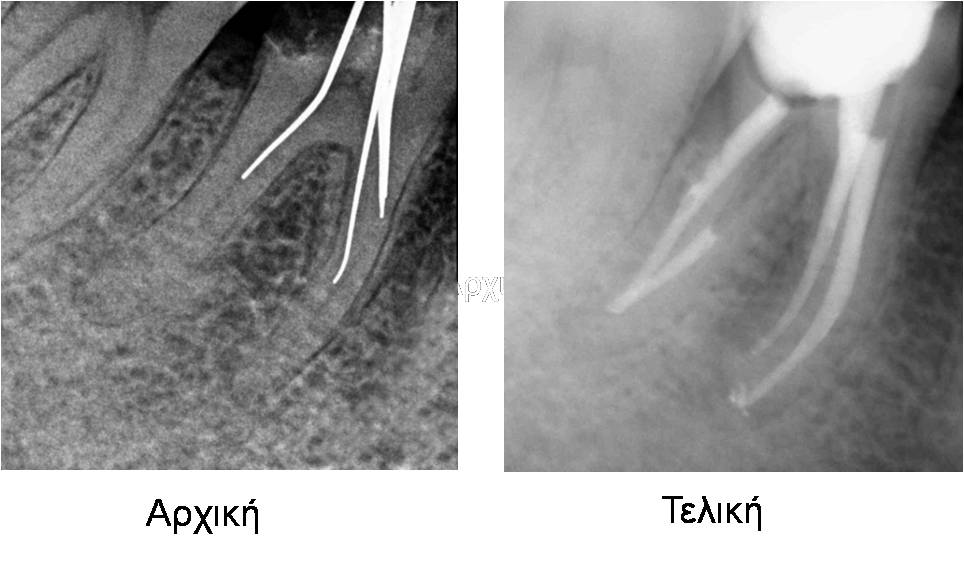

Περιστατικό 3

Αφαίρεση υπερέμφραξης

Περιστατικό 4

Αφαίρεση θραύσματος μικροεργαλείου